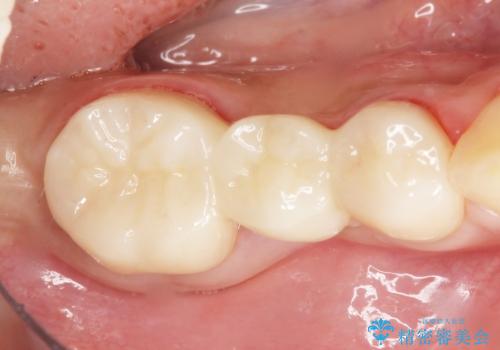

保存不可能な歯を抜去し、オールセラミックのブリッジによる補綴治療を行いました。

自然な仕上がりと咬み心地に喜んで頂けました。

プラークコントロール不良につき仮歯を精密に合わせても歯肉の腫脹を認めたため、工夫を凝らして精密な型取りを行うことで適合の良いクラウンを製作致しました。

クラウンの種類:ベレッツァクラウン